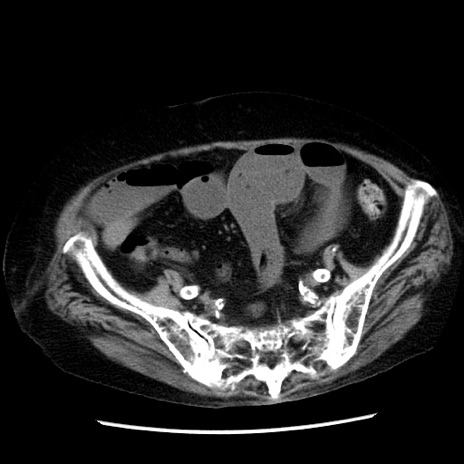

症例14(横断像)

【症例】 90歳代女性

【主訴】 腹痛・嘔吐

【現病歴】今朝から左側腹部痛を認めた。 経過観察していたが、嘔吐を認めたため来院。

【既往歴】 子宮癌術後

【身体所見】 意識清明、BP 127/54mmHg、P 98bpm Sp02 95%(RA)、BT 35.8°C、腹部平坦・軟腸ぜん動音聴取良好、右下腹部圧痛(+) 反跳痛なし

【データ】WBC 9800、CRP 0.46